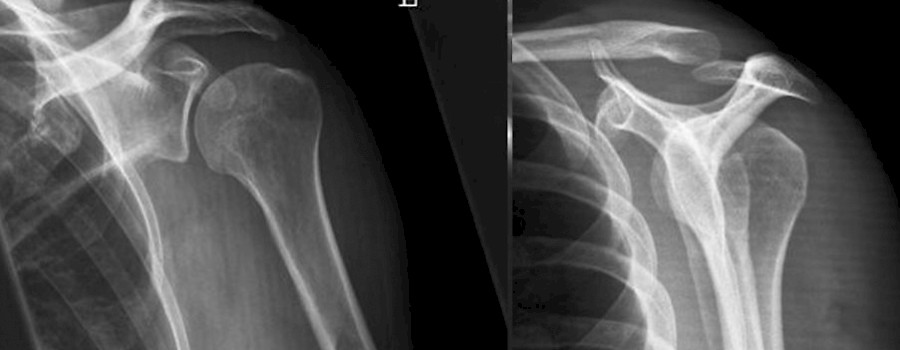

Bei der relativ großen Anzahl von möglichen Schultereinstellungen in der Röntgendiagnostik ist es nicht immer einfach und ganz klar, bei welcher Indikation welche Projektion die Fragestellung am Besten beantwortet.